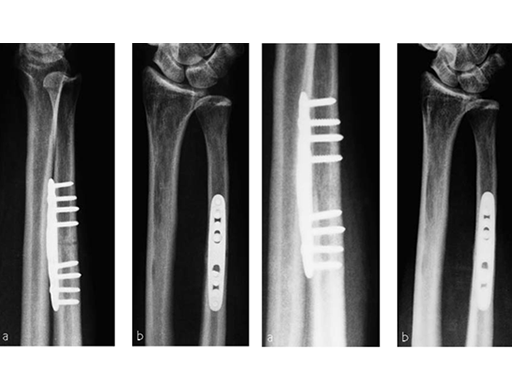

Case 3: Oblique osteotomy

A 48-year-old female nurse had a diagnosis of a degenerative central TFCCrupture, with chronic ulnocarpal abutment.

The amount of correction required was 2.5 mm. The preoperative x-ray showed positive ulna variance.